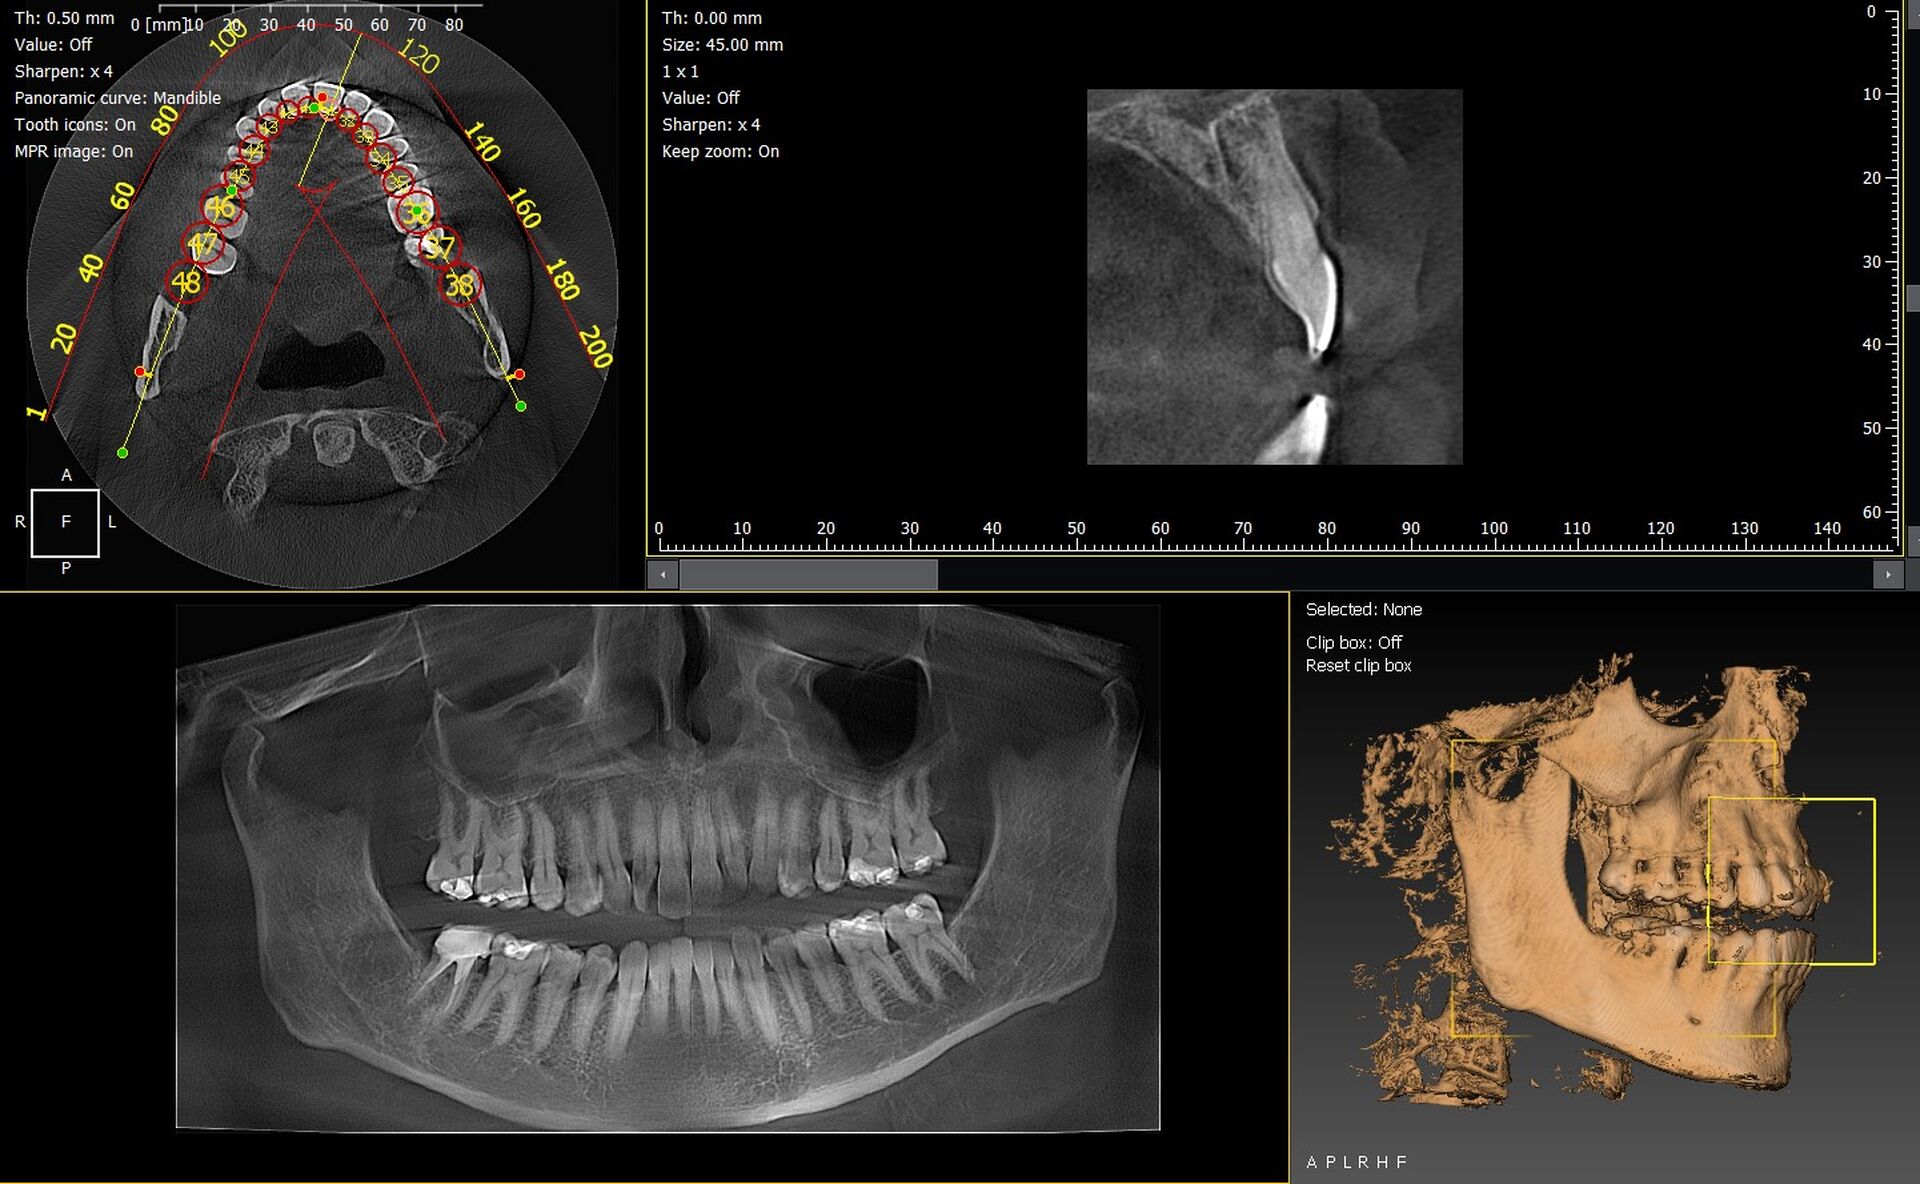

Les cabinets dentaires de Château Arnoux Saint Auban et du département des Alpes de Haute Provence 04 recherchent des solutions d’imagerie 2D/3D fiables pour renforcer la précision de leurs diagnostics. Les technologies CBCT permettent aujourd’hui une visualisation volumétrique détaillée, indispensable en implantologie, chirurgie orale, endodontie ou orthodontie. Parmi les appareils les plus performants du marché, les modèles Dürr Dental VistaVox et Owandy I-Max 3D offrent une qualité d’image exceptionnelle, une ergonomie moderne et une intégration simple dans les cabinets dentaires locaux.

Le VistaVox est reconnu pour sa précision diagnostique et son volume d’acquisition optimisé pour l’arcade complète. Grâce à sa technologie avancée, il fournit des images haute résolution permettant d’identifier clairement le canal mandibulaire, les sinus, les structures péri-apicales et les zones osseuses complexes.

• Images 3D haute définition avec faible dose de rayonnement.

• Champ d’acquisition adapté à l’implantologie et à la chirurgie.